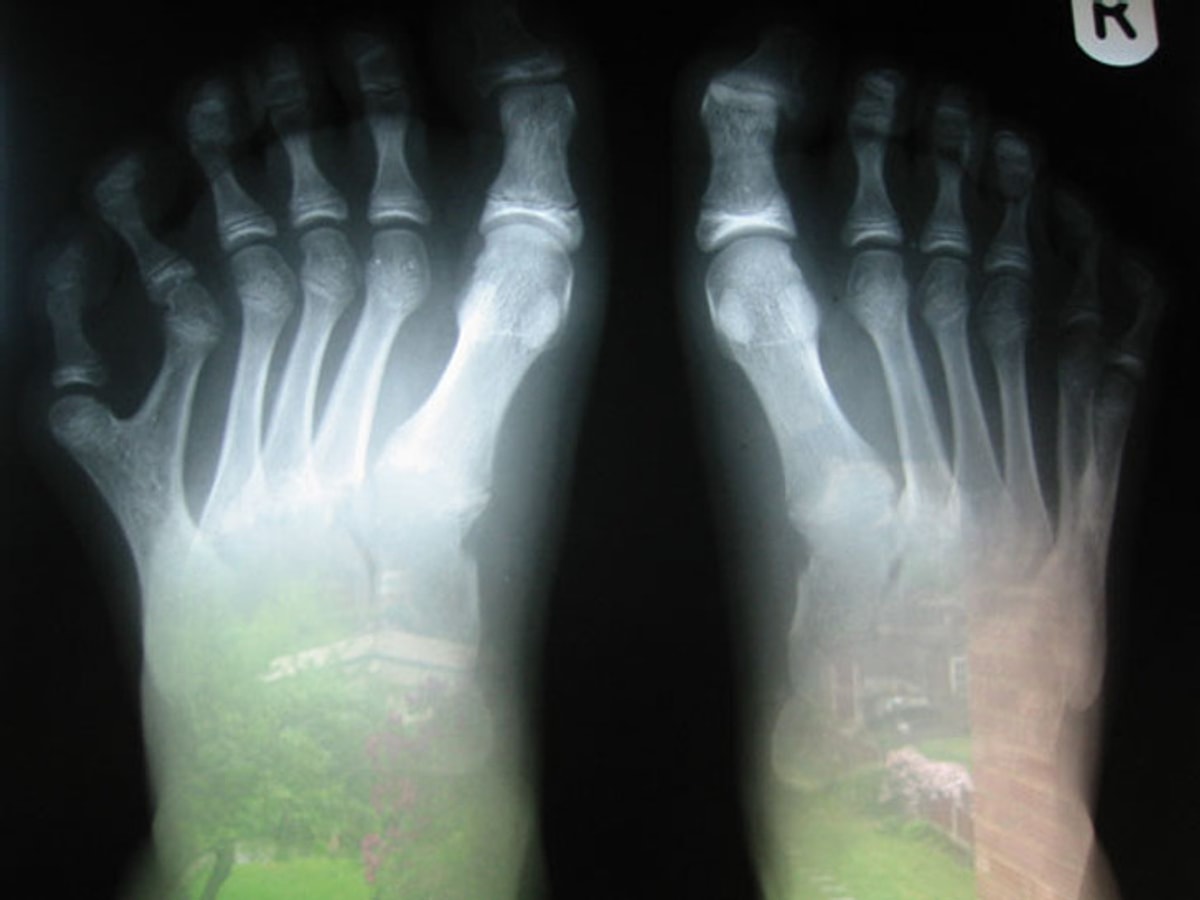

Родился без пальца

Родился без пальца 108 фотографий